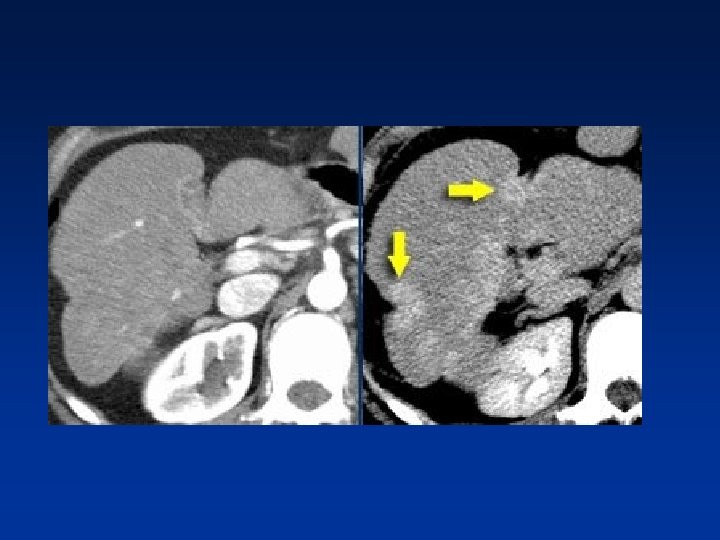

• Any hypervascular lesion in a cirrhotic liver is hepatocellular carcinoma untill proven otherwise. • HCC may be solitary, multifocal or diffusely infiltrating. • Large HCC typically have a mosaic appearance due to hemorrhage & fibrosis.

• HCC is a silent tumor, so if patients don’t have cirrhosis or hepatitis C , you will discover them in a late stage. • They tend to be large with mozaic pattern , a capsule , hemorrhage and necrosis. • HCC become isodense or hypodense to liver in the portal venous phase due to fast wash-out • On delayed images, the capsule and sometimes septa demonstrate prolonged enhancement.

• Large HCC with mozaic pattern in a non cirrhotic liver

HCC & PV thrombosis Many patients with cirrhosis have portal venous thrombosis and many patients with HCC have thrombosis. These are two common findings and they can be coincidental. It is very important to make the distinction between just thrombus and tumor thrombus. First, if you have a malignant thrombus in the portal vein, it will always enhance and you'll see it best in arterial phase. Secondly, if you have a malignant thrombus in the portal vein, it will increase the diameter of the vessel. Sometimes a tumor thrombus may present with neovascularity within the thrombus.

• Above : diffusely enhancing tumor thrombus in HCC with portal venous thrombosis. • Down: tumor thrombus with vessels within the thrombus